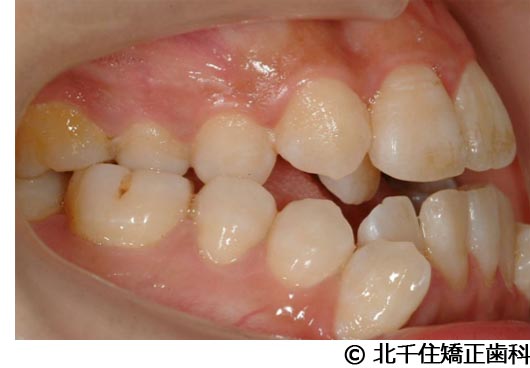

【症例4】下顎前突

- 治療前

- 治療後

- 治療名

- 下顎前突

- 費用

- 1,226,000円(税込)

- 期間

- 2年10ヵ月

- 治療回数

- 32回

- 通院頻度

- 1ヵ月ごと

- 年齢・性別

- 28歳5ヵ月・女性(初診時)

治療内容

-

患者様の症状

主訴:デコボコ、笑顔のとき歯がきれいに見えるようにしたい

治療方法

骨格性の下顎前突および開咬、上顎第二小臼歯と下顎第一小臼歯4本抜歯してワイヤー矯正(セラミックブラケット)。

治療結果

骨格性下顎前突および開咬に対し、抜歯を併用した矯正治療により歯列および咬合関係の調整を行った症例である。治療後は保定装置を使用し、歯列および咬合の安定維持を目的として定期的な経過観察を行っている。

※治療結果は個人差があります。

治療を行う上での注意点(リスク・副作用)

歯磨き不良に伴うカリエスや歯周病、歯根吸収など。